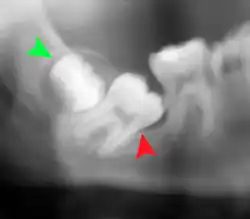

Coronectomy

Coronectomy is a procedure where the crown of the impacted wisdom tooth is removed, but the roots are intentionally left in place. It is indicated when there is no disease of the dental pulp or infection around the crown of the tooth, and there is a high risk of inferior alveolar nerve injury.[32]

Coronectomy, while lessening the immediate risk to the inferior alveolar nerve function has its own complication rates and can result in repeated surgeries. Between 2.3% and 38.3% of roots loosen during the procedure and need to be removed and up to 4.9% of cases require reoperation due to persistent pain, root exposure or persistent infection. The roots have also been reported to migrate in 13.2% to 85.9% of cases.[32]